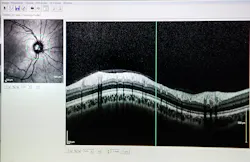

Many SD-OCT devices on the market are used to image disorders of the retina and the anterior segment of the eye. For example, SD-OCT is used to detect glaucoma, an eye disease that damages the optic nerve due to an increase in pressure from fluid buildup.

When using SD-OCT, a thickness map of the retinal nerve fiber layer, as seen in Figure 4, can be formed to understand the severity of glaucoma and track its progression.1 SD-OCT can also be paired with surgical platforms such as laser eye surgery or phacoemulsification procedures to provide real-time images for the surgeon.